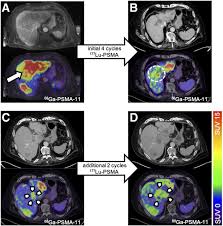

Clinical Characteristics And Prognostic Factors Of Prostate Cancer With Liver Metastases Semantic Scholar

Clinical Characteristics And Prognostic Factors Of Prostate Cancer With Liver Metastases Semantic Scholar from d3i71xaburhd42.cloudfront.net